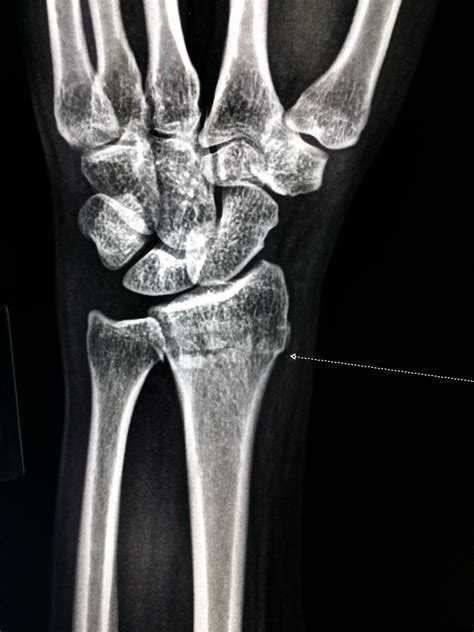

A Wrist Bones Xray is a valuable diagnostic tool for evaluating various conditions and injuries affecting the wrist. This imaging technique uses X-rays to produce detailed images of the bones and joints, allowing healthcare professionals to identify fractures, dislocations, and other abnormalities. Some of the key benefits of a Wrist Bones Xray include:

• Diagnosing Fractures: X-rays can detect fractures in the wrist bones, including hairline fractures that may not be visible on physical examination.

• Evaluating Joint Alignment: X-rays can help assess the alignment of the wrist joints, identifying dislocations or subluxations.

• Trauma: Following a wrist injury, such as a fall or a direct blow, an X-ray can help determine the extent of the damage.

Interpreting the results of a Wrist Bones Xray requires the expertise of a radiologist or orthopedic specialist. The images will be reviewed to identify any abnormalities or injuries. Some common findings on a wrist X-ray include:

• Fractures: Visible breaks or cracks in the bones.

• Dislocations: Misalignment of the bones in the wrist joint.